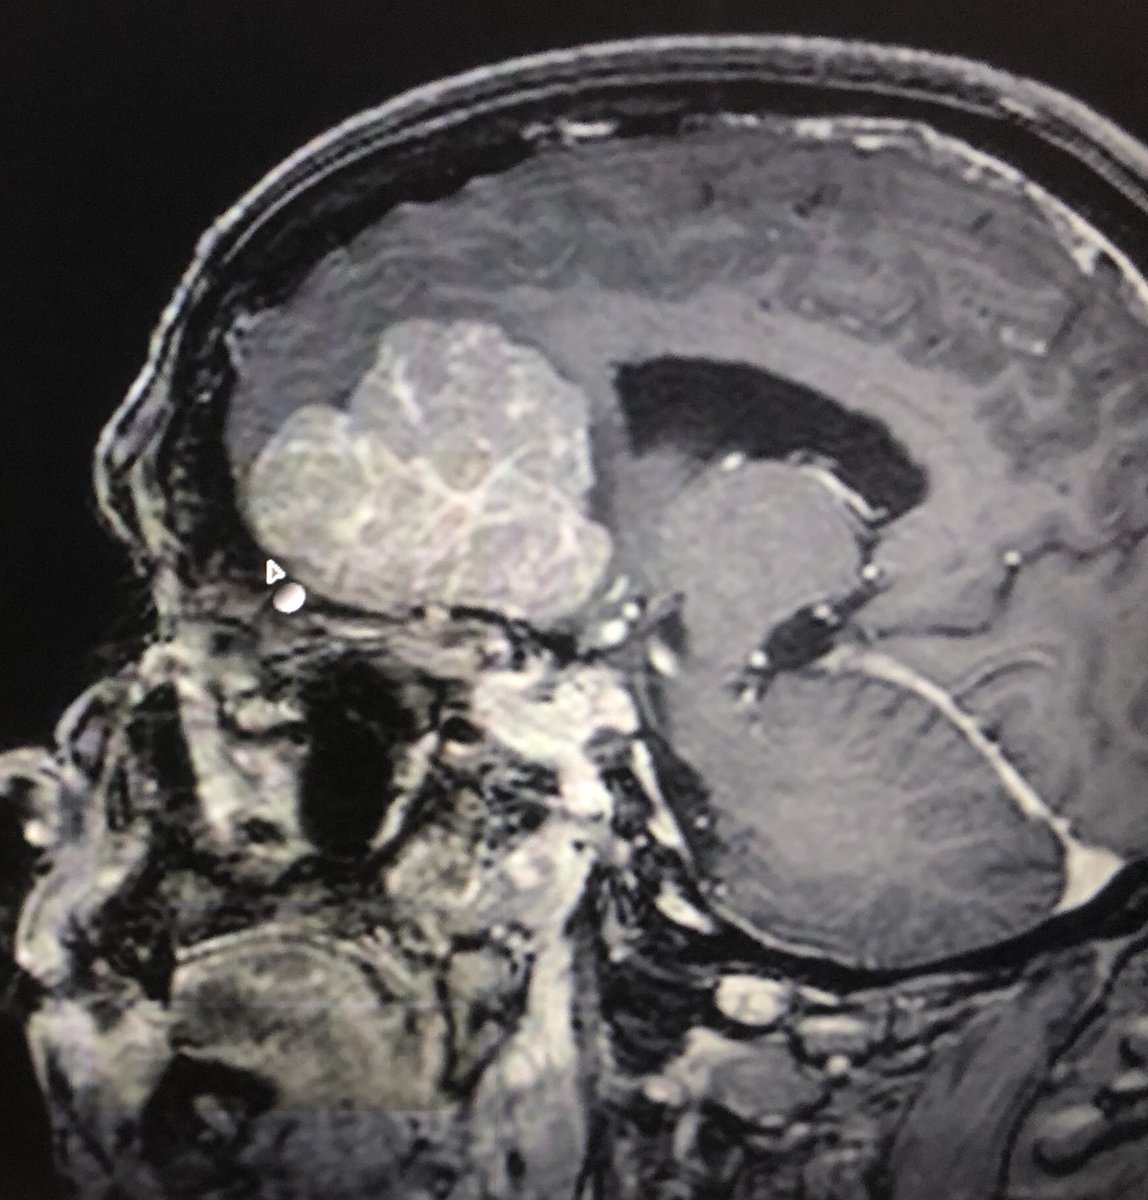

Fabulous to push the boundaries of #glioblastoma treatment with @johnboockvar @lenoxhill @NorthwellHealth and read about positive response of Daniel https://t.co/IK5nsuneIp using #EnGeneIC EDV tech.

We are currently enrolling #GBM patients for our EnGeneIC Dream Vector (EDVTM) nanocell-based technology, a new way of delivering chemotherapy drugs for the treatment of #braintumors. https://t.co/EUGTQusUoq @LenoxNeurosurg @NorthwellHealth 4 info please contact @ShereseFralin

Congrats to our @LenoxNeurosurg #braintumor research team for treating our first patient in @EnGeneIC EDV trial for #gbm @BrainCancerCure